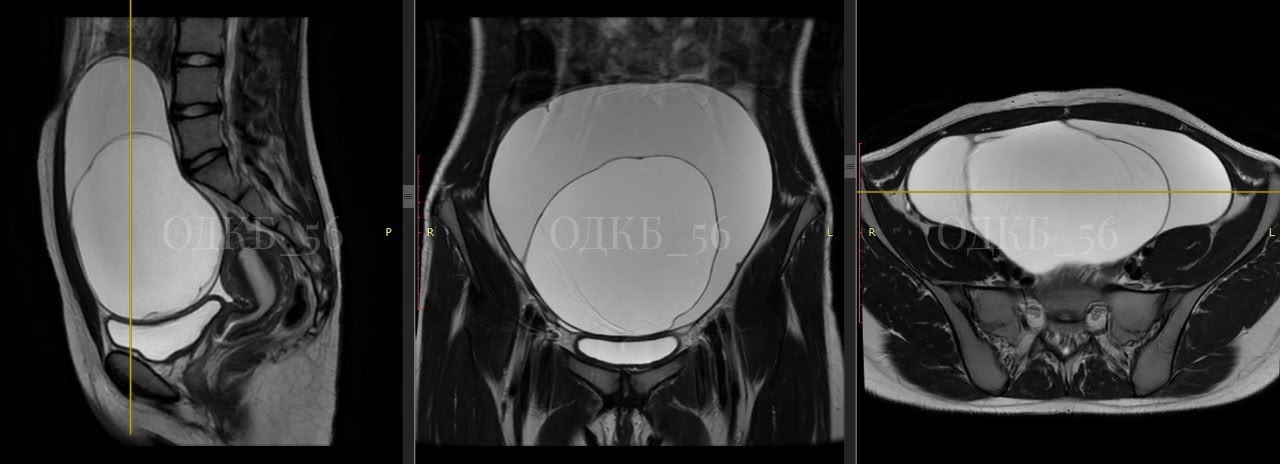

Девочка поступила в экстренное приёмное отделение с сильными болями в животе. Осмотр и последующие УЗИ и МРТ выявили объемное образование диаметров около 20 см, после чего девочку в срочном порядке прооперировали.

«К счастью, образование, оказалось доброкачественным, был выставлен диагноз: муцинозная цистаденома правого яичника. Девочка восстановилась за неделю и выписана в удовлетворительном состоянии» - отметила специалист.